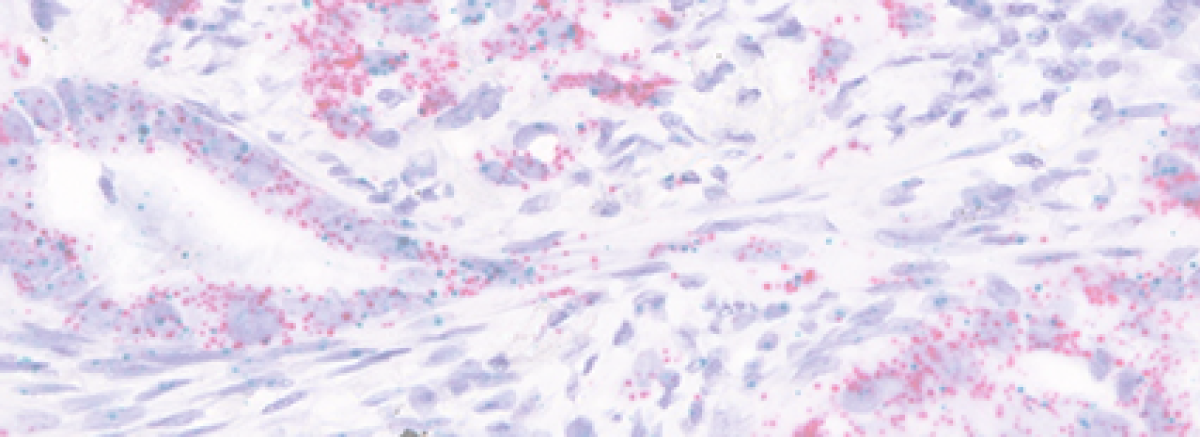

RNA splice variants | Circular RNA | Point mutations |

EGFRvIII (Glioblastoma) | DLGAP1 circRNA (Hippocampal CA3) | KRAS-G12C mutation (SW-1573 cell) |